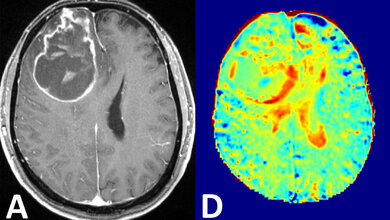

Der Einzelantrag des Zentrums für Bildgebung am Ulmer Universitätsklinikum wurde kürzlich von der Deutschen Forschungsgemeinschaft (DFG) bewilligt. Das kombinierte PET/MRT-Gerät wird im Laufe des Jahres 2018 zentral am Standort Oberer Eselsberg platziert – am Schnittpunkt der Neuen Chirurgie, der Inneren Medizin, der Nuklearmedizin und der Radiologie. So profitieren alle Disziplinen von kurzen Wegen zum neuen Hybrid-Gerät. Durch die hochauflösende Darstellung aller Gewebe- und Organstrukturen sowie deren Funktionen können die Forschungen aller Fachbereiche vorangetrieben werden. „Bei simultaner Durchführung eines MRTs und eines PETs können wir einen noch tieferen und präziseren Blick in die Funktionen des Gehirns oder die Biologie von Tumoren werfen. So wollen wir beispielsweise die Aggressivität von Tumoren nicht-invasiv noch genauer bestimmen, um die Therapie des Patienten individuell angepasst zu steuern“, beschreiben die Mediziner die Vorteile des neuen Hybridgeräts. „Hat man genaue Erkenntnisse über das Verhalten des Tumors, lässt er sich zielgerichteter behandeln – das ist gelebte Präzisionsmedizin.“ Mit der Aufnahme von Patientenuntersuchungen wird ebenfalls im Verlauf des nächsten Jahres gerechnet. (idw, red)